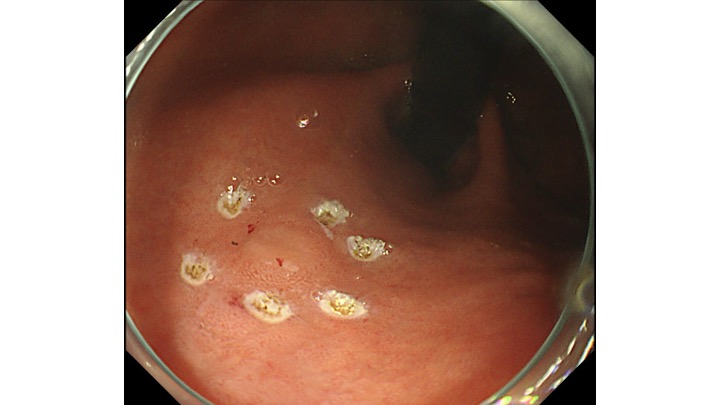

電気メスでマーキングをして、わずか8分で内視鏡治療終了しております。

内視鏡治療エキスパートのクリニックであれば、胃癌の内視鏡治療(ESD)は入院せず、日帰り治療の時代が到来したと考えております。